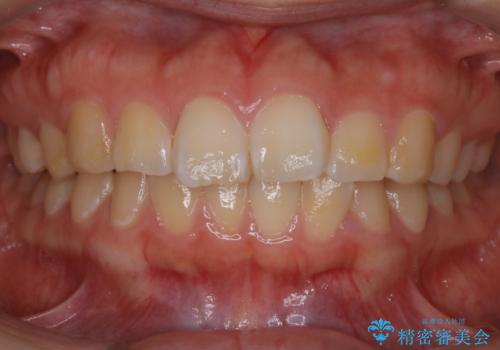

【非抜歯】ガタつきと歯軸を正して長持ちする歯へ

- 歯のガタつきと噛み合わせの改善を主訴に来院されました。

非抜歯で、少量の奥歯の移動と歯列の拡大・IPRを駆使して主訴を改善するための治療計画を立案しました。